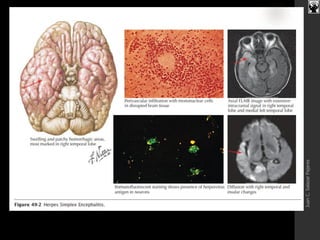

ENCEFALITIS HERPETICA

 Es la más frecuente: 1-3/millón Hb. en

occidente.

 La mortalidad llega al 70-80% sin

tratamiento

 Todos los supervivientes presentan

secuelas.

 El patógeno habitual : H. simple 1.

 En RN e inmunosuprimidos puede ser

causado por el H. simple 2.

 La mayoría se debe a reactivación de una

infección endógena.